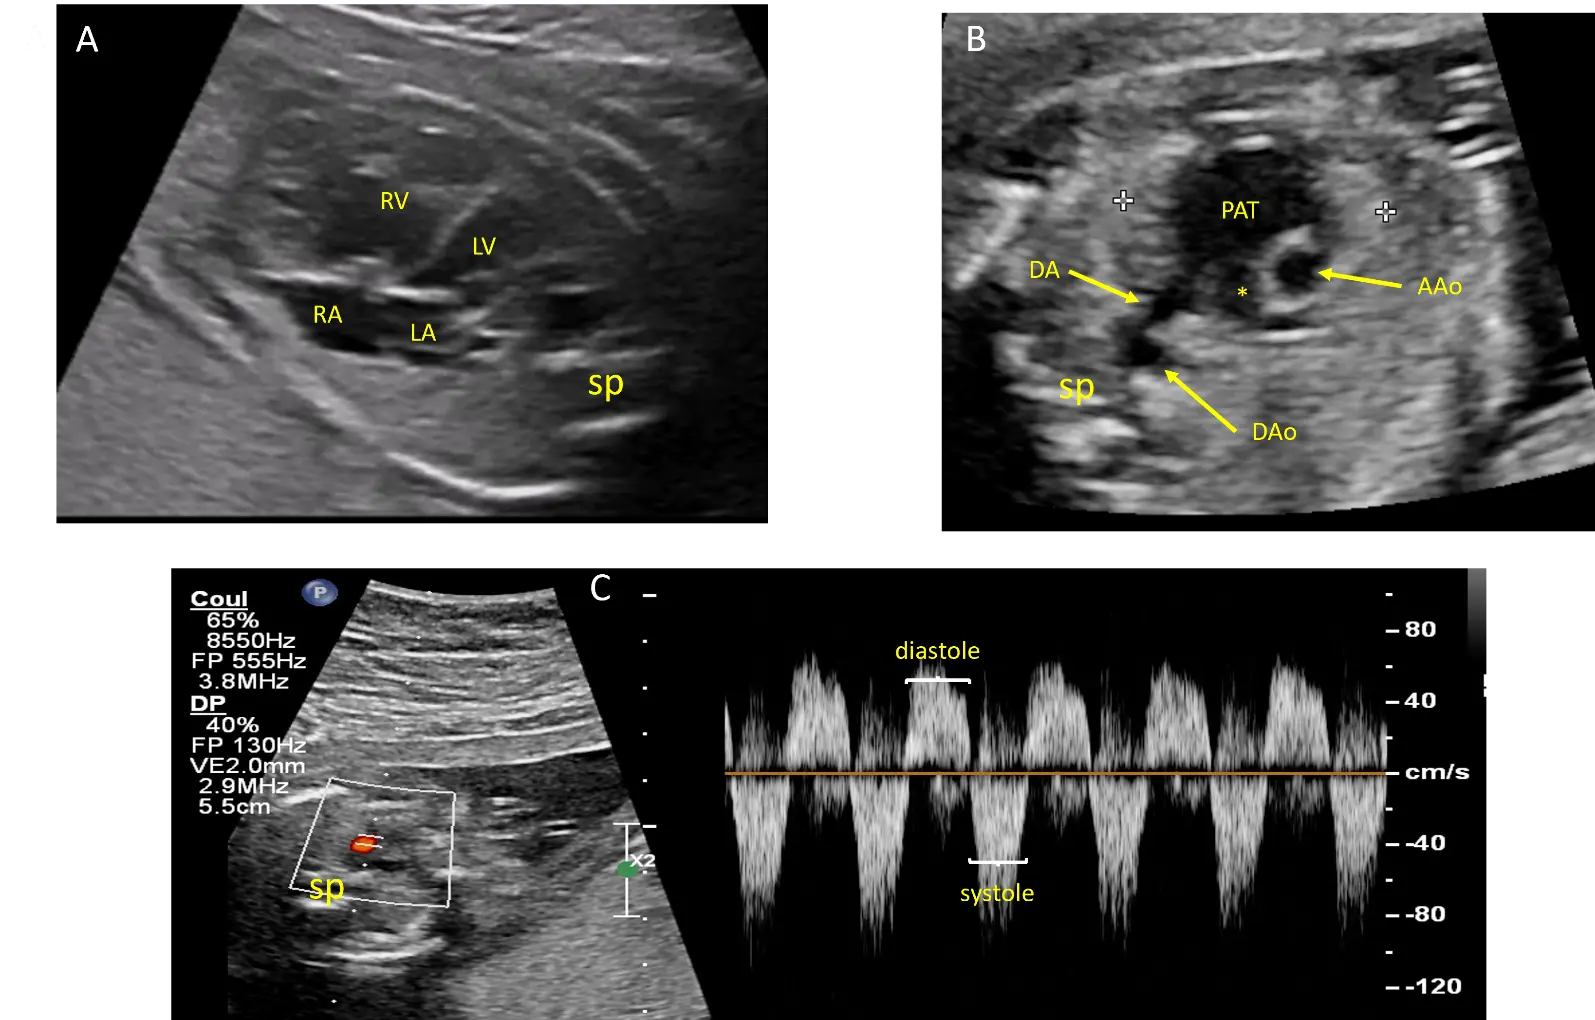

Fetal echocardiography revealed asymmetric cardiomegaly and a leftward deviation of the heart axis by 90°, attributed to right ventricular dilatation (Video S1). The pulmonary valves were rudimentary, and while the main pulmonary trunk was significantly dilated, the pulmonary branches showed only mild dilatation (Figure 1A,B). Doppler studies demonstrated to-and-fro blood flow across the pulmonary orifice with severe pulmonary regurgitation, as well as reverse flow during diastole through a widely patent ductus arteriosus (Figure 1C) (Video S2). There was no tricuspid regurgitation. The aortic arch was normally oriented to the left, and there was no pericardial effusion. The thymus was of normal size.

Figure 1. Echocardiographic views from case #1 at 21 weeks of gestation: Four chamber view showing cardiomegaly with dilatation of the right ventricle (RV) and leftward deviation of the heart axis (A). Short axis view of the great arteries showing dilatation of the pulmonary artery trunk (PAT) but not of the right pulmonary artery (*). The 2 calipers (white crosses) delimitate the thymus (B). Pulsed doppler flow on the ductus arteriosus showing an antegrade flow during systole and a reverse flow during diastole (C). AAo: ascending aorta, DA: ductus arteriosus, DAo: descending aorta, LA: Left atrium, LV: left ventricle, RA: right atrium, sp: spine.